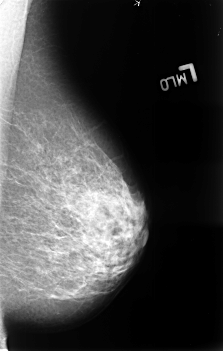

B_3399_1.RIGHT_MLO

RIGHT_MLO LINES 4552 PIXELS_PER_LINE 2928 BITS_PER_PIXEL 12 RESOLUTION 50 OVERLAY